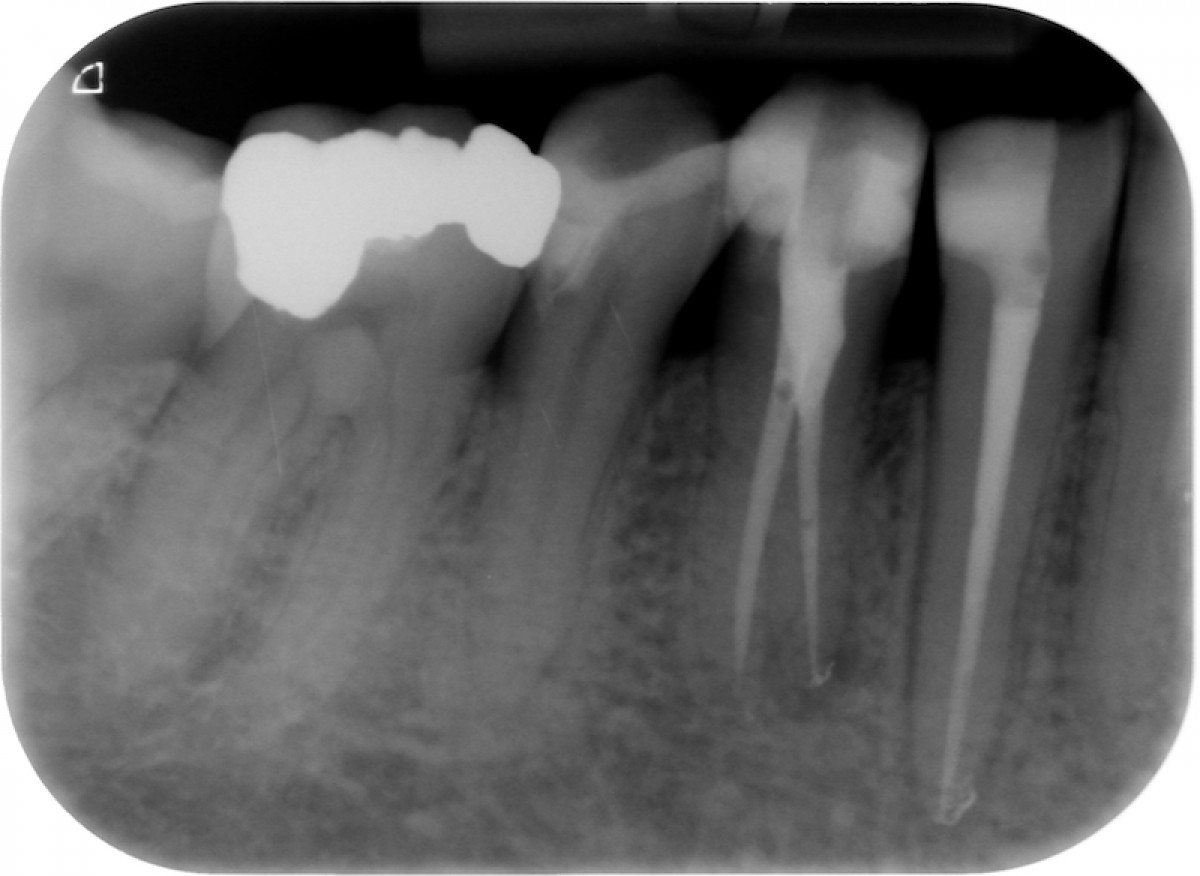

The gutta-percha point inserted into the root canal properly, adapting it to a size almost equal to the one employed to shape the apical terminus. Not wider, not smaller. Here are exposed a couple of cases made by shaping the root canal with a NiTi instrumentation technique and followed up for 9 to 12 months (Fig. 1-6).

It’s encouraging its easy handling and quite precise adaptation to the apical part of the root canal. The periapical healing, assessed by 2D-Rx, is considered satisfactory but further analysis and clinical studies related to these particular cements should be performed to confirm the first encouraging results.